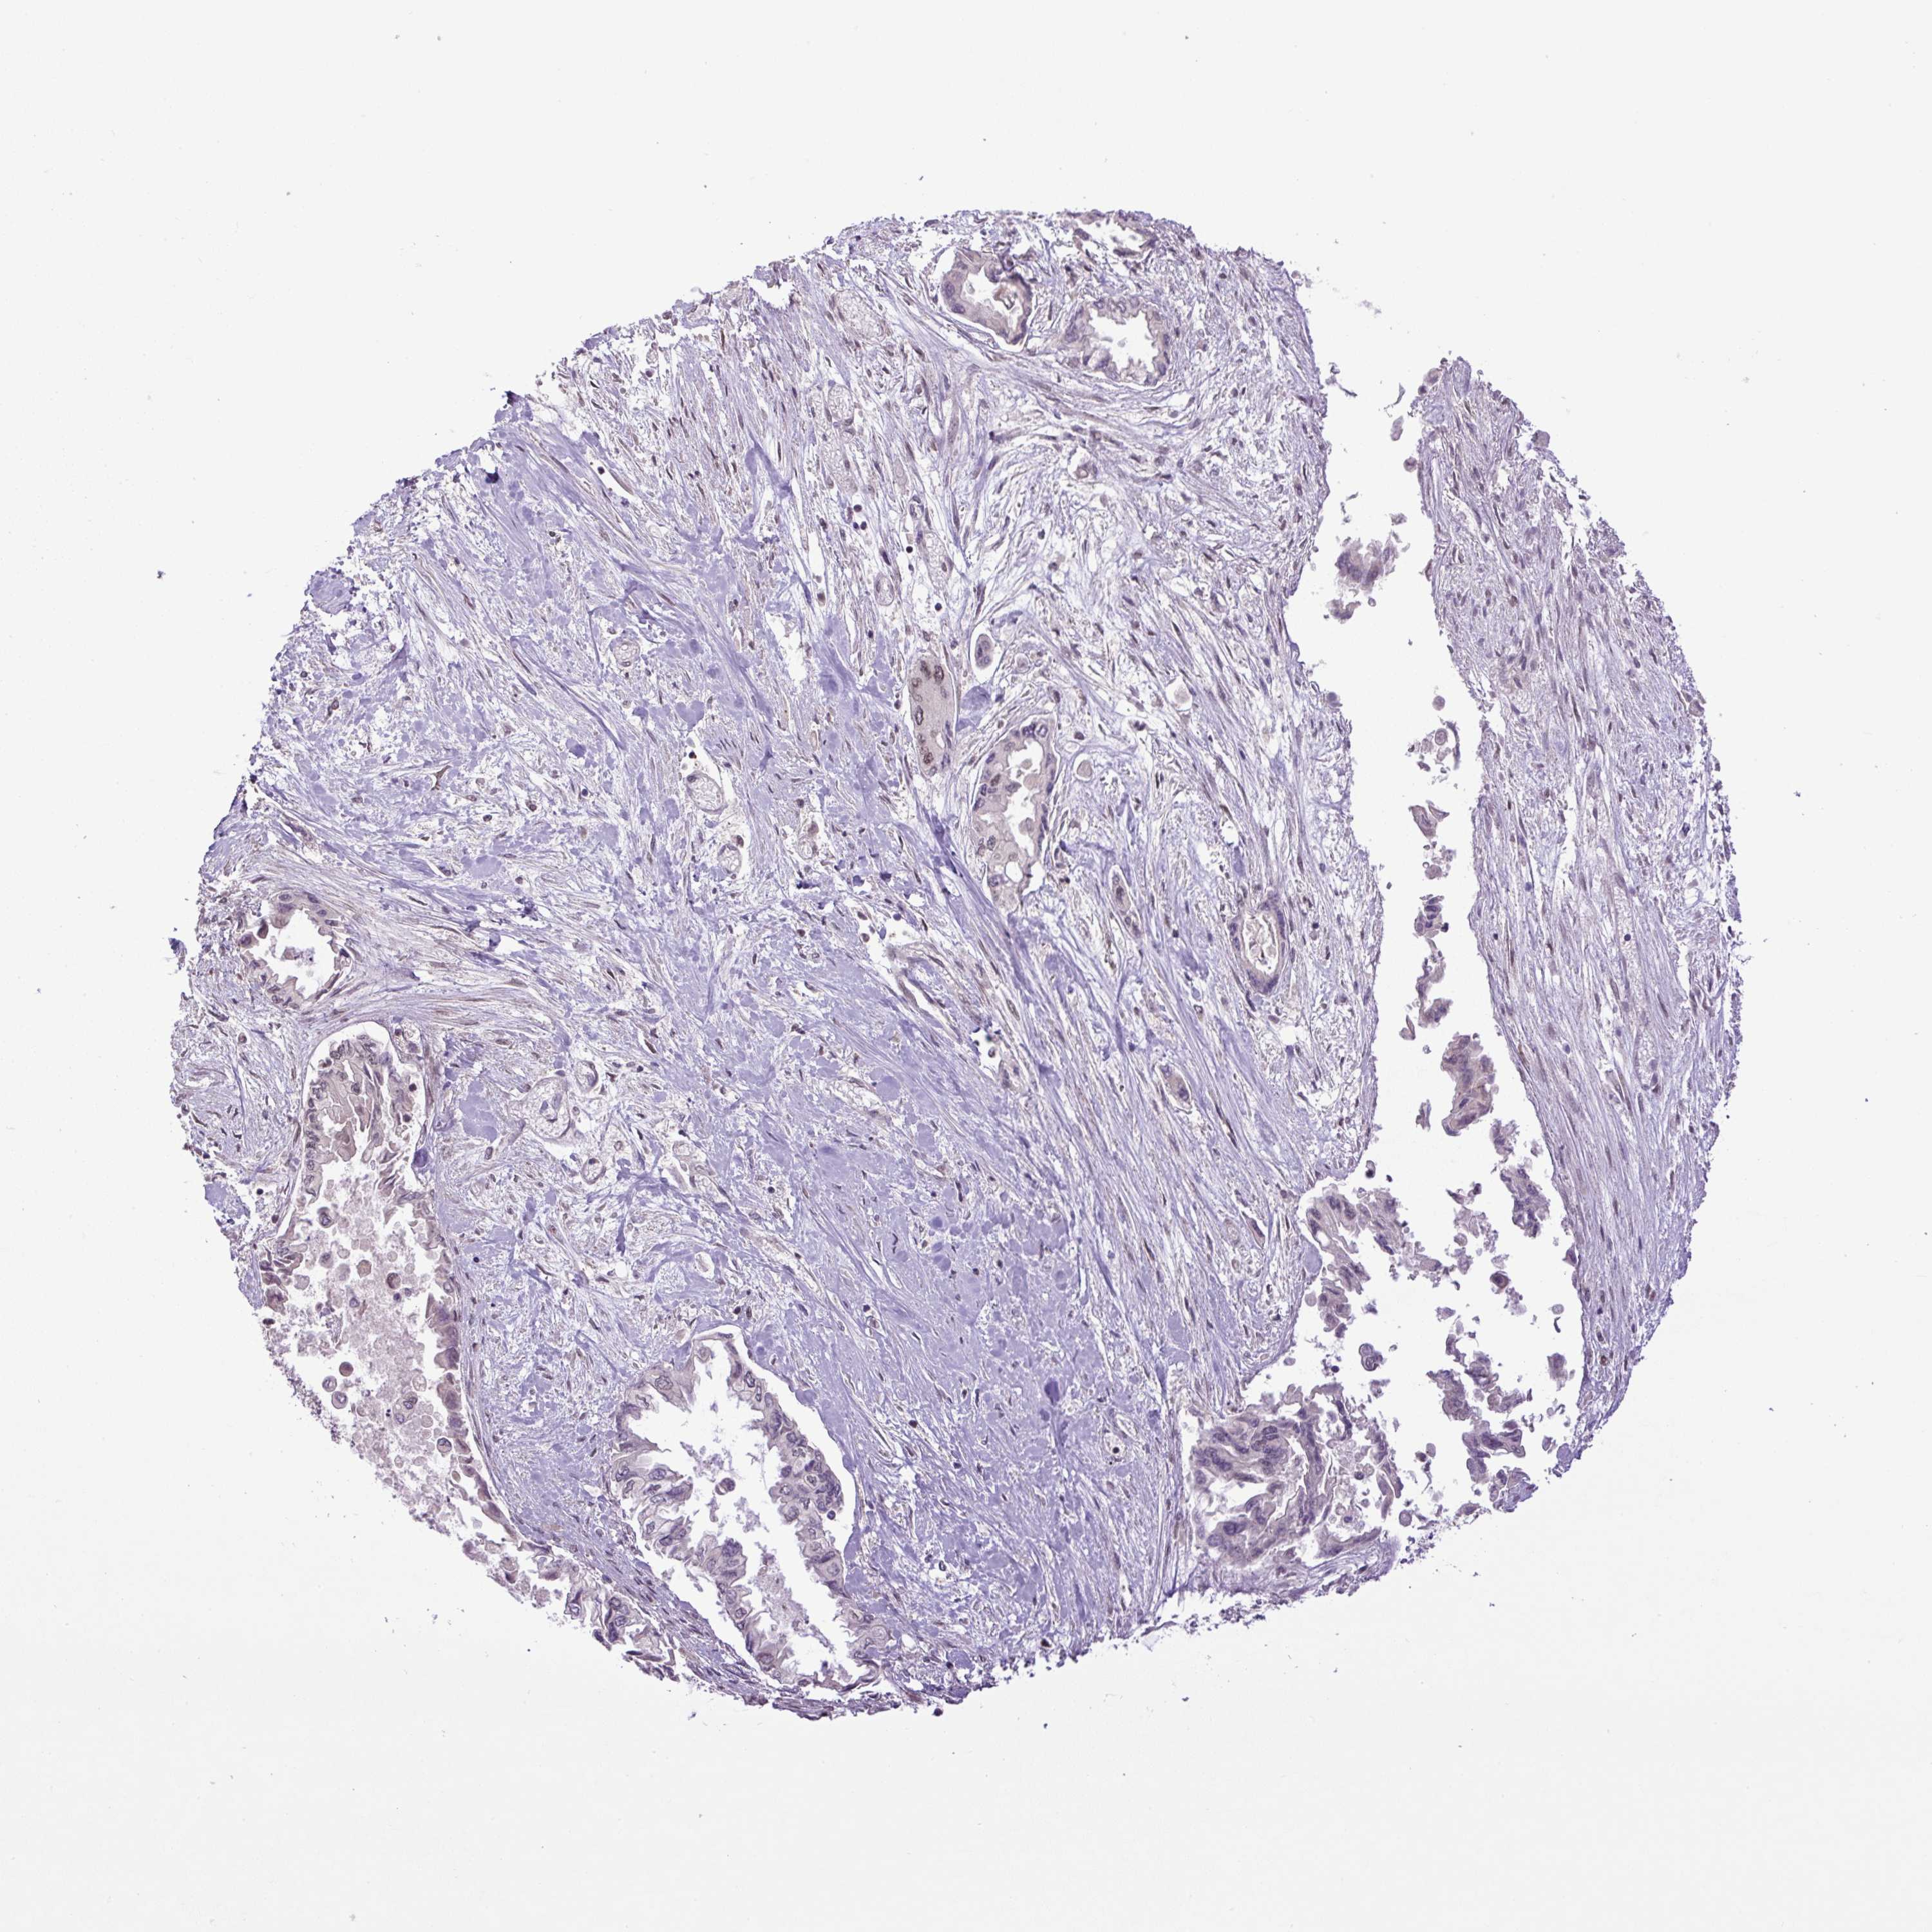

PANCREATIC CANCER - Protein expressioni

A mouse-over function shows sample information and annotation data. Click on an image to view it in a full screen mode. Samples can be filtered based on level of antibody staining by selecting one or several of the following categories: high, medium, low and not detected. The assay and annotation is described here.

Note that samples used for immunohistochemistry by the Human Protein Atlas do not correspond to samples in the TCGA dataset.

Antibody stainingi

Antibody staining in the annotated cell types in the current human tissue is reported as not detected, low, medium, or high, based on conventional immunohistochemistry profiling in selected tissues. This score is based on the combination of the staining intensity and fraction of stained cells.

Each image is clickable and will lead to virtual microscopy that enables deeper exploration of all samples and also displays staining intensity scores, fraction scores and subcellular localization as well as patient and tissue information for each sample.

Antibody HPA053627

Staining

High

Medium

Low

Not detected

Intensity

Strong

Moderate

Weak

Negative

Quantity

>75%

75%-25%

<25%

None

Location

Nuclear

Cytoplasmic/membranous

Cytoplasmic/membranous,nuclear

Adenocarcinoma, NOS